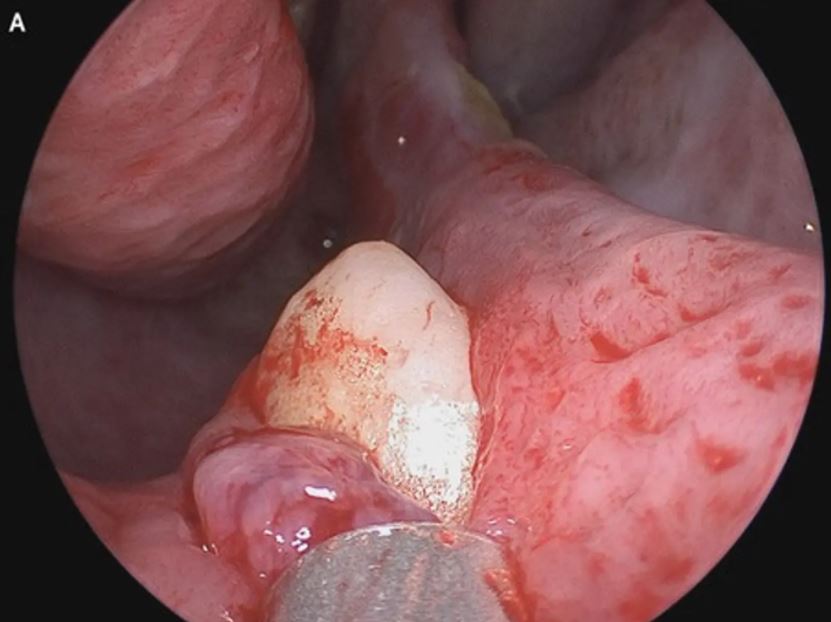

Lelaki itu yang mengunjungi Mount Sinai Health System di New York telah menjalani ujian rinoskopi menggunakan kamera kecil yang dimasukkan ke dalam lubang hidung kanannya.

Hasil pemeriksaan menemui gigi ektopik, iaitu gigi yang tumbuh di tempat tidak normal berukuran sepanjang 15.24 sentimeter.

Penemuan yang dibuat pakar bedah Dr. Sagar Khanna dan Michael Turner ini juga telah diterbitkan dalam New England Journal of Medicine (NEJM).

Lelaki itu kemudiannya menjalani pembedahan bagi mengeluarkan gigi tersebut. Akhirnya, beliau mampu bernafas secara normal melalui kedua-dua lubang hidungnya tanpa sebarang komplikasi.